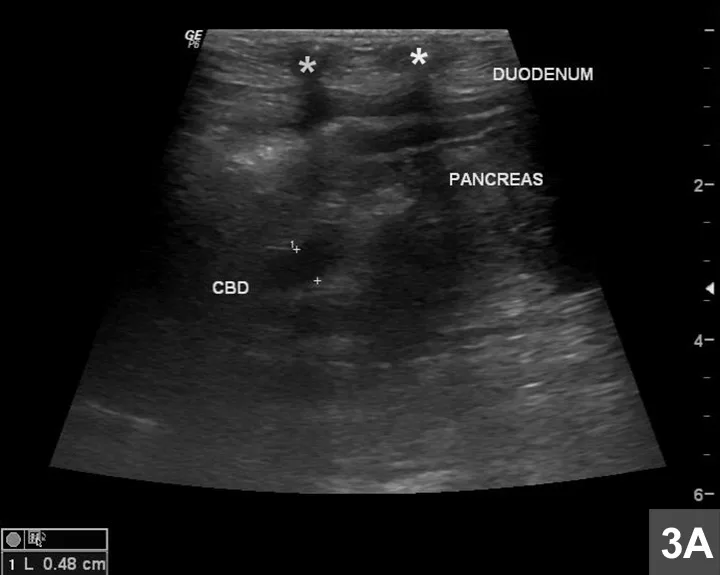

Featured Image

Figure 3A

The common biliary duct (CBD) is outlined by + markers while asterisks indicate the ribs.

On ultrasound imaging, the liver appears to be subjectively enlarged. The gallbladder appears severely distended with anechoic fluid; the cystic duct (0.60 cm in diameter) and common bile duct (CBD; 0.48 cm) adjacent to the right pancreatic lobe also appear distended (Figure 3A). Note that the ribs are causing beam attenuation. In addition, normal and abnormal diameters in dogs have not been reported; however, in one study in cats, extrahepatic biliary obstruction was involved when the ultrasonographic diameter of the CBD measured <5 mm.1